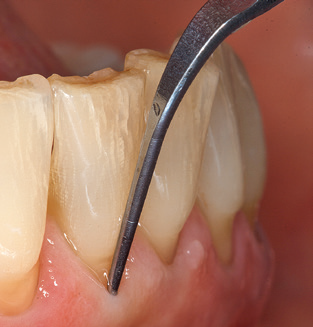

Good illumination of the working field facilitates the process considerably. The system used by the authors achieves this thanks to a 5x LED ring integrated in the handpiece. Naturally, a range of working tips for different indications is also offered. A straight, universally employable tip is the basic instrument required for machine cleaning of natural teeth (Fig. 5a and b). Curved tips, which allow access to exposed furcations, are also available for hard-to-reach areas in the posterior region (Fig. 6).

Of course, working tips for the cleaning of implant surfaces are also indispensable for SPT in patients fitted with implants. The implant cleaning attachment on the system used here is characterised by its tapered, hexagonal design. This design allows light, atraumatic penetration of the peri-implant pocket and displays a good cleaning performance (Fig. 7).

Following machine cleaning of the tooth and implant surfaces, the surfaces of the natural teeth are cleaned manually using standard hand instruments. When performing manual cleaning, particular attention must be given to maintaining the correct angle of application, appropriate sharpness, good support and working with the curette from apical to coronal. Either titanium or carbon curettes should be used for post-cleaning of the implant structures (Fig. 8). In addition to the use of ultrasonic devices, power jet devices can also be used in conservative dentistry. However, it must be taken into consideration that these procedures are not suitable for removing hard deposits and thus they cannot replace the use of hand instruments and ultrasonic instruments completely. In all cases, cleaning is followed by mechanical polishing of the accessible tooth and implant surfaces with polishing cups and polishing compounds (Fig. 9).